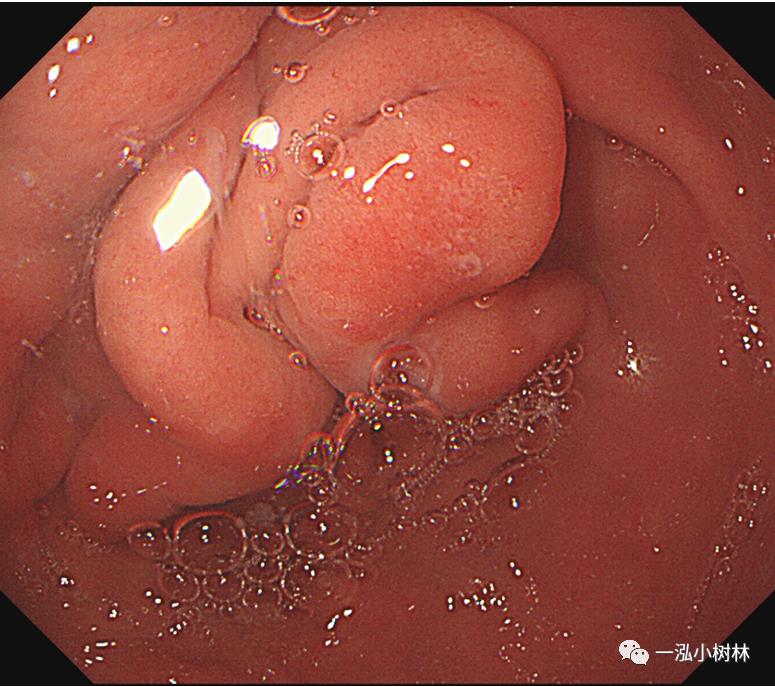

例7 胃窦病变

图7 白光内镜:胃窦后壁高-中分化腺癌(Tub1>Tub2)